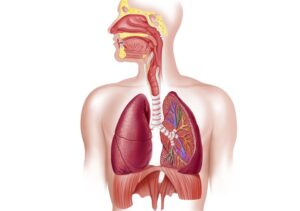

6. The Respiratory System

Anatomy of breathing (lungs, diaphragm, airways)

Gas exchange and oxygen transport

Effects of massage on breathing and recovery